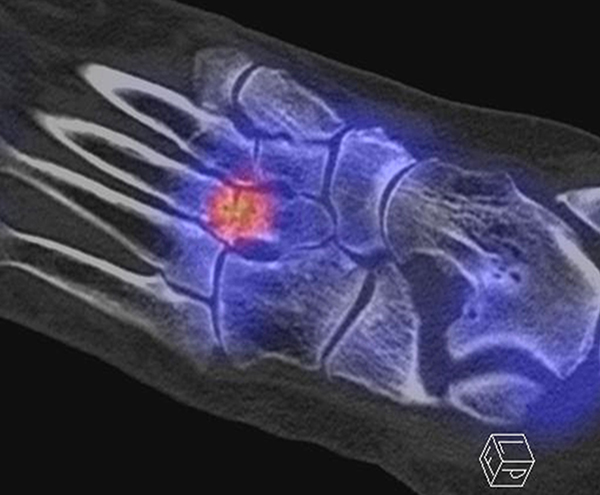

Abbildung 1.6.

Bekannte Gicht mit Polyarthralgien. Am rechten Großzehengrundgelenk lateral in der Grundphalanx entzündliche Erosionen.

Abbildung 1.7.

Gichtarthritis mit Osteolysen und flauen Verkalkungen in den periartikulären Weichteilen/Gelenkkapsel.

Abbildung 1.8.

Abbildung 1.8.a und b: Akute Arthritis bei bekannter Gicht in beiden OSG: links die Früh-/Weichteilphase; rechts die Mineralisations­phase. Deutliche, entzündlich bedingte Mehranreicherungen in der Früh-/Weichteilphase. In der Mineralisation­sphase erkennt man die entzündliche Mitreaktion der subchondralen Gelenkabschnitte.

Zum Lesen der Bildbeschreibung und zur Vollansicht bitte das Bild anklicken. Bild: H. C. Rischke

Abbildung 1.8.c - e: Akute Arthritis in beiden OSG, rechts > links. Im SPECT/CT erkennt man die Mitreaktion der subchondralen Gelenkabschnitte. Die Arthritis ist so akut, dass (noch) keine ossären morphologischen Veränderungen im CT abgrenzbar sind.

Zum Lesen der Bildbeschreibung und zur Vollansicht bitte die Bilder anklicken. Bilder: H. C. Rischke